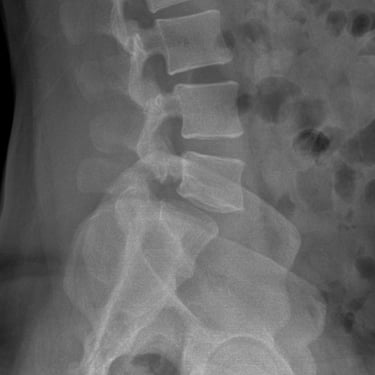

Listesis Lumbar L5–S1 por Fractura Ístmica: Estabilización con FTP y TLIF

La listesis lumbar L5–S1 por fractura ístmica se produce por un defecto en la pars interarticularis que genera inestabilidad vertebral, dolor lumbar crónico y compromiso radicular. Cuando el tratamiento conservador no es efectivo, la artrodesis lumbar con fijación transpedicular (FTP) asociada a la fusión intersomática transforaminal (TLIF) es una alternativa quirúrgica eficaz. Este procedimiento permite descomprimir las raíces nerviosas, restaurar la alineación vertebral y lograr una fijación sólida del segmento afectado. La combinación de estabilización y fusión reduce el dolor, mejora la función y favorece una recuperación segura y progresiva.